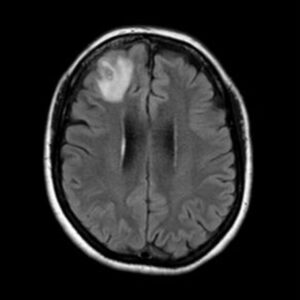

A woman in Australia’s New South Wales was diagnosed with a rare and bizarre infection after suffering from unexplained abdominal pain, diarrhea, night sweats, and a persistent cough. Despite a battery of tests—checking for bacteria, fungi, human parasites, and autoimmune diseases—doctors found no answers. But weeks later, a CT scan of her chest revealed something moving in her lungs, and an MRI of her brain turned up a glowing spot in the frontal lobe.

A baffling medical mystery has been solved in Australia after doctors discovered a live snake parasite in a woman’s brain. The woman, who had been battling unexplained symptoms like abdominal pain, a dry cough, and fatigue for months, underwent multiple tests—all of which came back negative. However, a CT scan later revealed a moving spot in her lungs, and an MRI of her brain uncovered a strange glowing area.